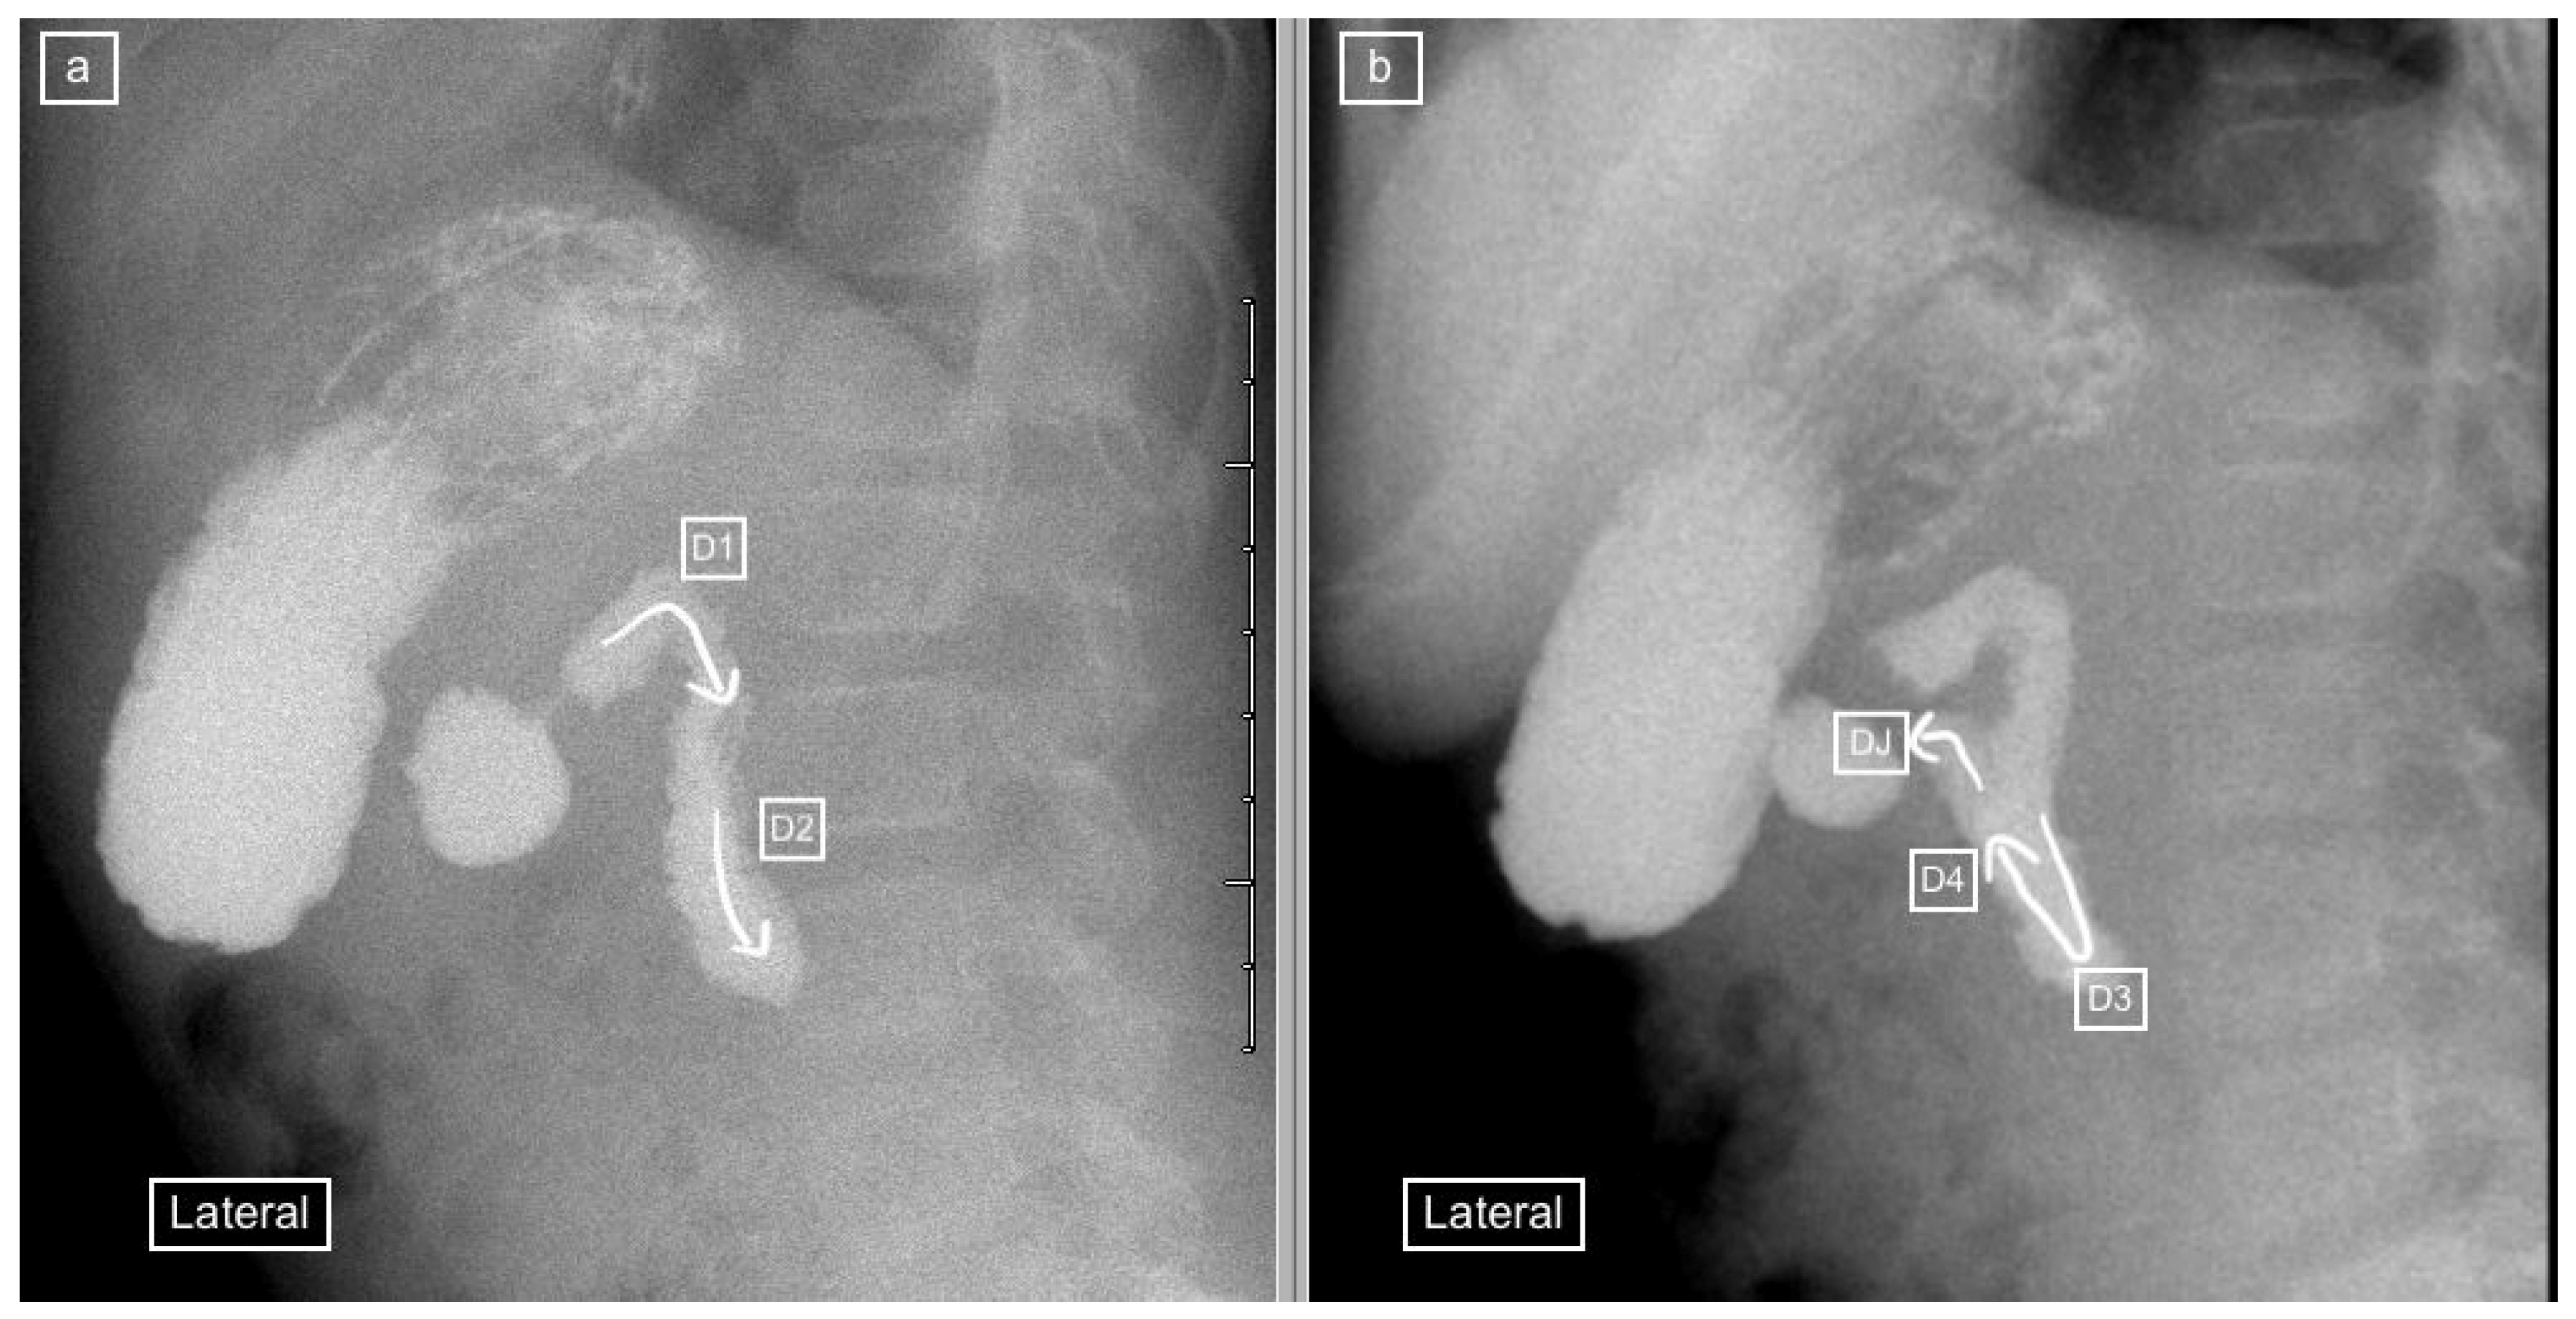

Figure 1.

(a) early and (b) later view: Sequential lateral views from an upper gastrointestinal tract study (UGIS) in an 8-year-old boy demonstrating the normal configuration of the duodenum which courses posteriorly (retroperitoneal) from the antrum (D1), descends posteriorly (D2), remains posterior at its most inferior portion (D3), ascends posteriorly again through (D4) and only then courses anteriorly from the duodeno-jejunal (DJ) flexure at the same height as the antrum and D1.